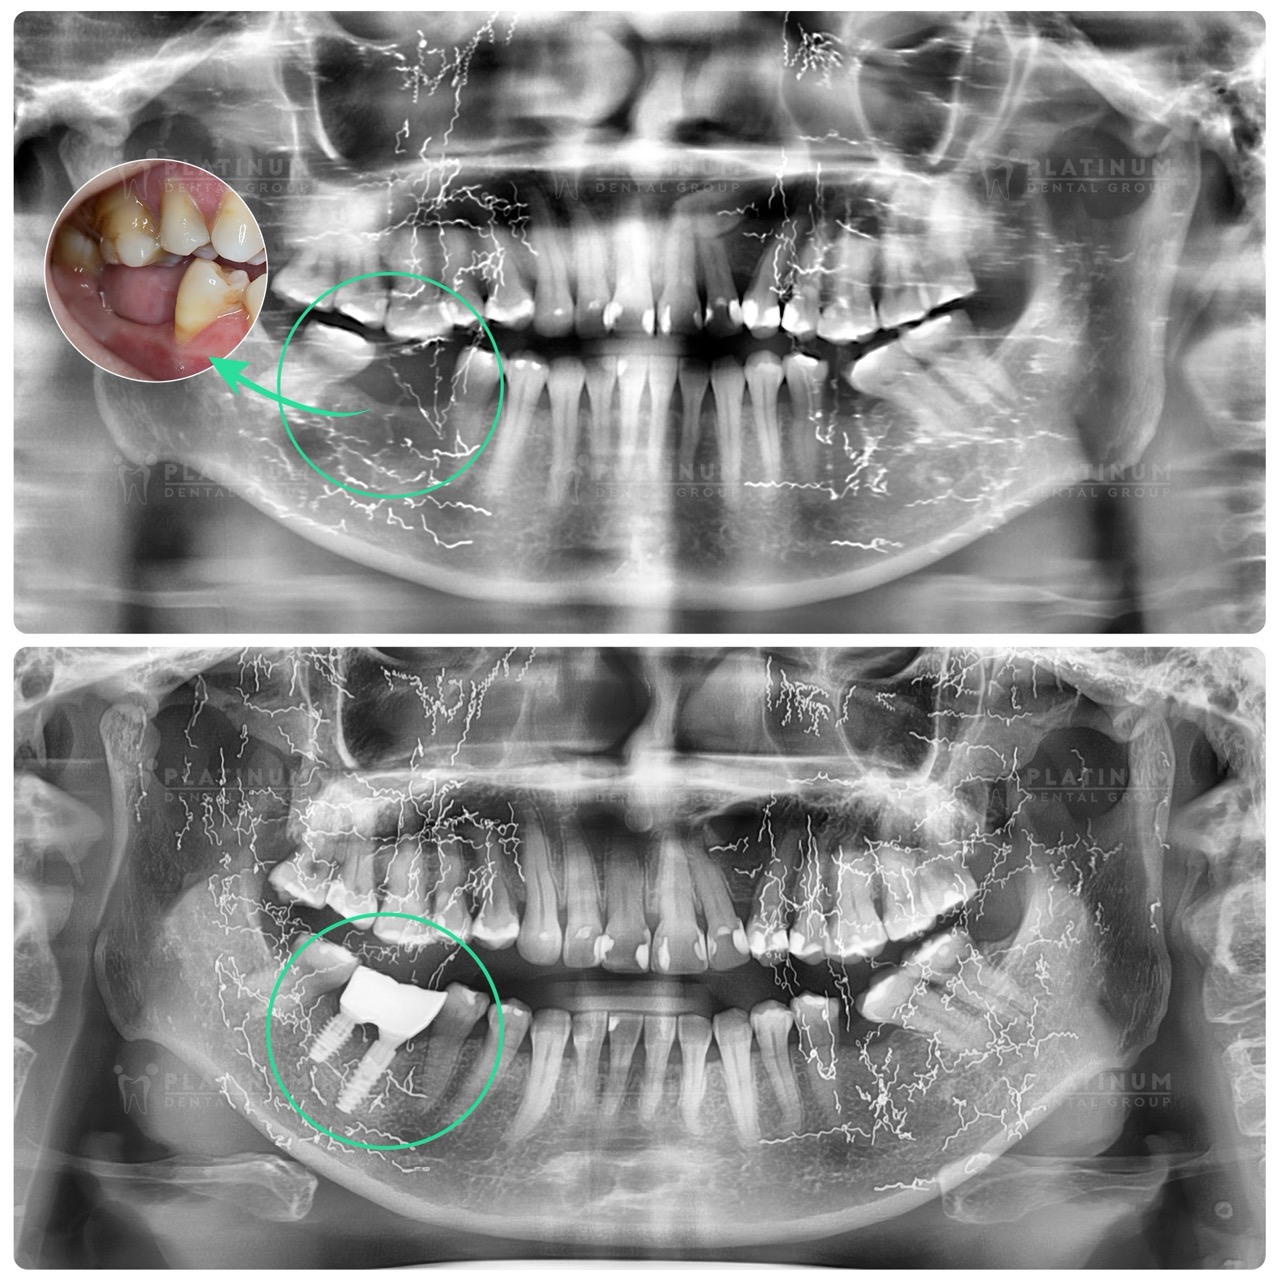

Sau khi thăm khám lâm sàng kỹ lưỡng, đặc biệt là phân tích hình ảnh chuyên sâu bằng máy 3D Conebeam CT, scan răng 3D, bác sĩ Tùng đã tư vấn và lên kế hoạch điều trị, phục hồi hai chiếc răng hàm đã mất cho cô Hà bằng phương pháp Implant đơn lẻ an toàn, hạn chế đau và hồi phục tốt.

- Tình trạng xương hàm đã bị tiêu do mất răng lâu năm, bác sĩ thực hiện ghép xương

- Cấy ghép 2 trụ Implant hàm dưới

- Răng tạm tức thì sau cấy ghép

- Phục hình răng sứ cố định sau 4 tháng chờ trụ tích hợp tốt

Chia sẻ về cảm nhận sau khi kết thúc hành trình trồng răng, cô Hà bày tỏ: “Lúc đầu thì cô cũng lo nhưng sau khi được bác sĩ Tùng cắm Implant không thấy đau, cô thấy yên tâm. Bây giờ có răng về ăn nhai cũng ổn, cô vui chứ lúc chưa làm tưởng tượng cô lo lắm”Để xóa bỏ lo lắng về một điều trị “phức tạp” như cô Hà hay nhiều cô chú lo lắng trước khi trồng răng: lo lắng cắm Implant có đau không, bác sĩ có làm tốt không, có bị biến chứng không,… Platinum Dental luôn tập trung vào hai tiêu chí: Kỹ thuật chuyên môn vững từ bác sĩ và ứng dụng tiến bộ công nghệ số:Quy trình trồng răng Implant chuẩn, do đội ngũ bác sĩ chuyên sâu có gần 20 năm kinh nghiệm cấy ghép Implant của Platinum trực tiếp thực hiện.Ứng dụng toàn diện công nghệ hiện đại tại phòng khám: Hệ thống chụp phim CBCT ghi nhận phim x-quang vùng xương hàm rõ ràng; Máy scan răng iTero 5D quét dấu răng chính xác, thoải mái, không nôn ói; máy quét ngoài mặt face scan hiện đại; Hệ thống định vị động cấy ghép Implant, xác định đúng vị trí cấy ghép, tránh các cấu trúc giải phẫu quan trọng (dây thần kinh, xoang hàm), rút ngắn thời gian cấy ghép trụ Implant; Máy quét dấu 3D trên Implant nhanh chính xác, thoải máiĐặc biệt, dòng trụ DIO bổ sung công nghệ UV, xử lý bề mặt trụ Implant trước khi cấy ghép, tăng độ sạch bề mặt implant được hoạt hóa, giúp xương tích hợp nhanh.Phục hình răng tức thì sau phẫu thuật Implant khoảng 2-3 giờ, đảm bảo có răng thẩm mỹ và ăn nhai ngay sau cấy ghép.Phục hình cố định sau cùng đảm bảo thẩm mỹ, chắc chắn, đúng khớp cắn để cô chú sử dụng ăn nhai như răng thật, thoải mái, bảo vệ trụ Implant.Việc này giúp đảm bảo ca cấy ghép được thực hiện đúng, chính xác, nhanh chóng mang đến trải nghiệm không đau, hạn chế sưng, hồi phục nhanh với kết quả Implant bền chắc, ăn nhai như răng thật. Toàn bộ quy trình được thực hiện nhẹ nhàng trong khoảng gần một tiếng, cô Hà có răng tạm ngay sau 2 giờ phẫu thuật, đảm bảo không trống răng.